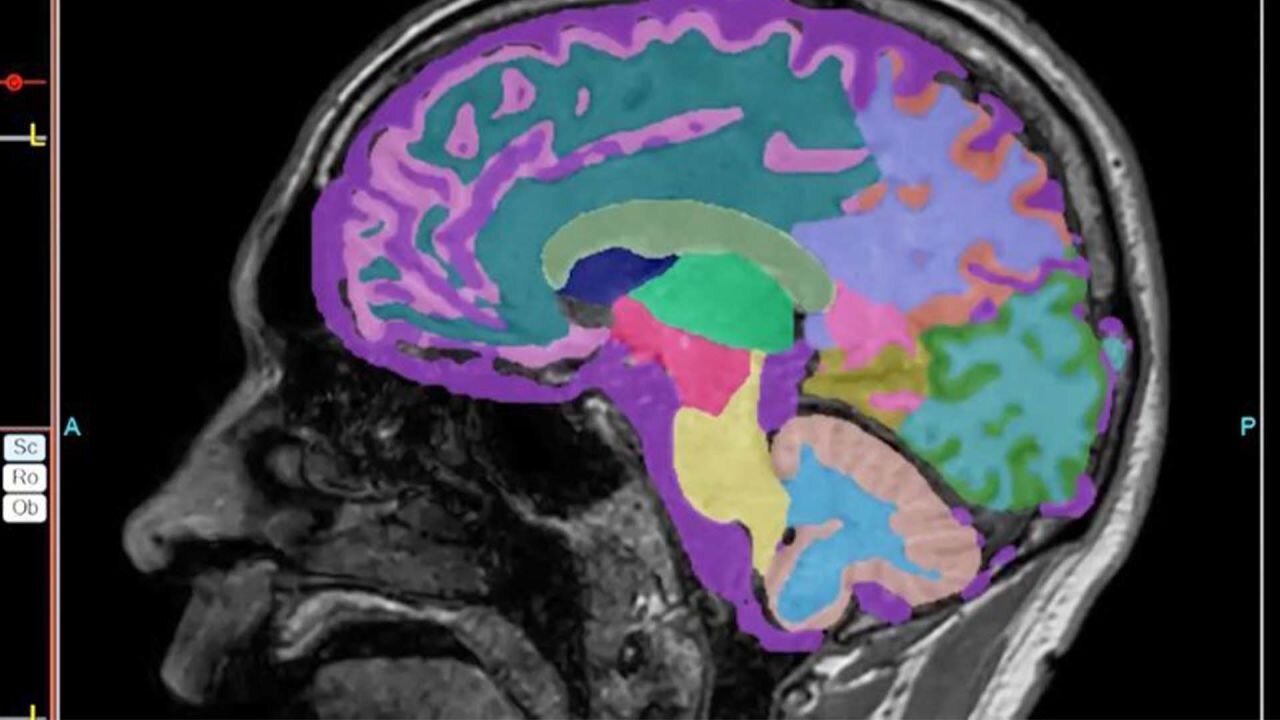

Un nuevo y prometedor estudio científico ha arrojado luz sobre uno de los aspectos más desgarradores del Alzheimer: la pérdida de la memoria social.

Investigadores de la Universidad de Virginia (UVA) han identificado un mecanismo molecular clave que explica por qué los pacientes comienzan a olvidar a sus familiares y amigos, un descubrimiento que no solo ofrece respuestas a pacientes y cuidadores, sino que también abre la puerta a un tratamiento con medicamentos ya existentes.